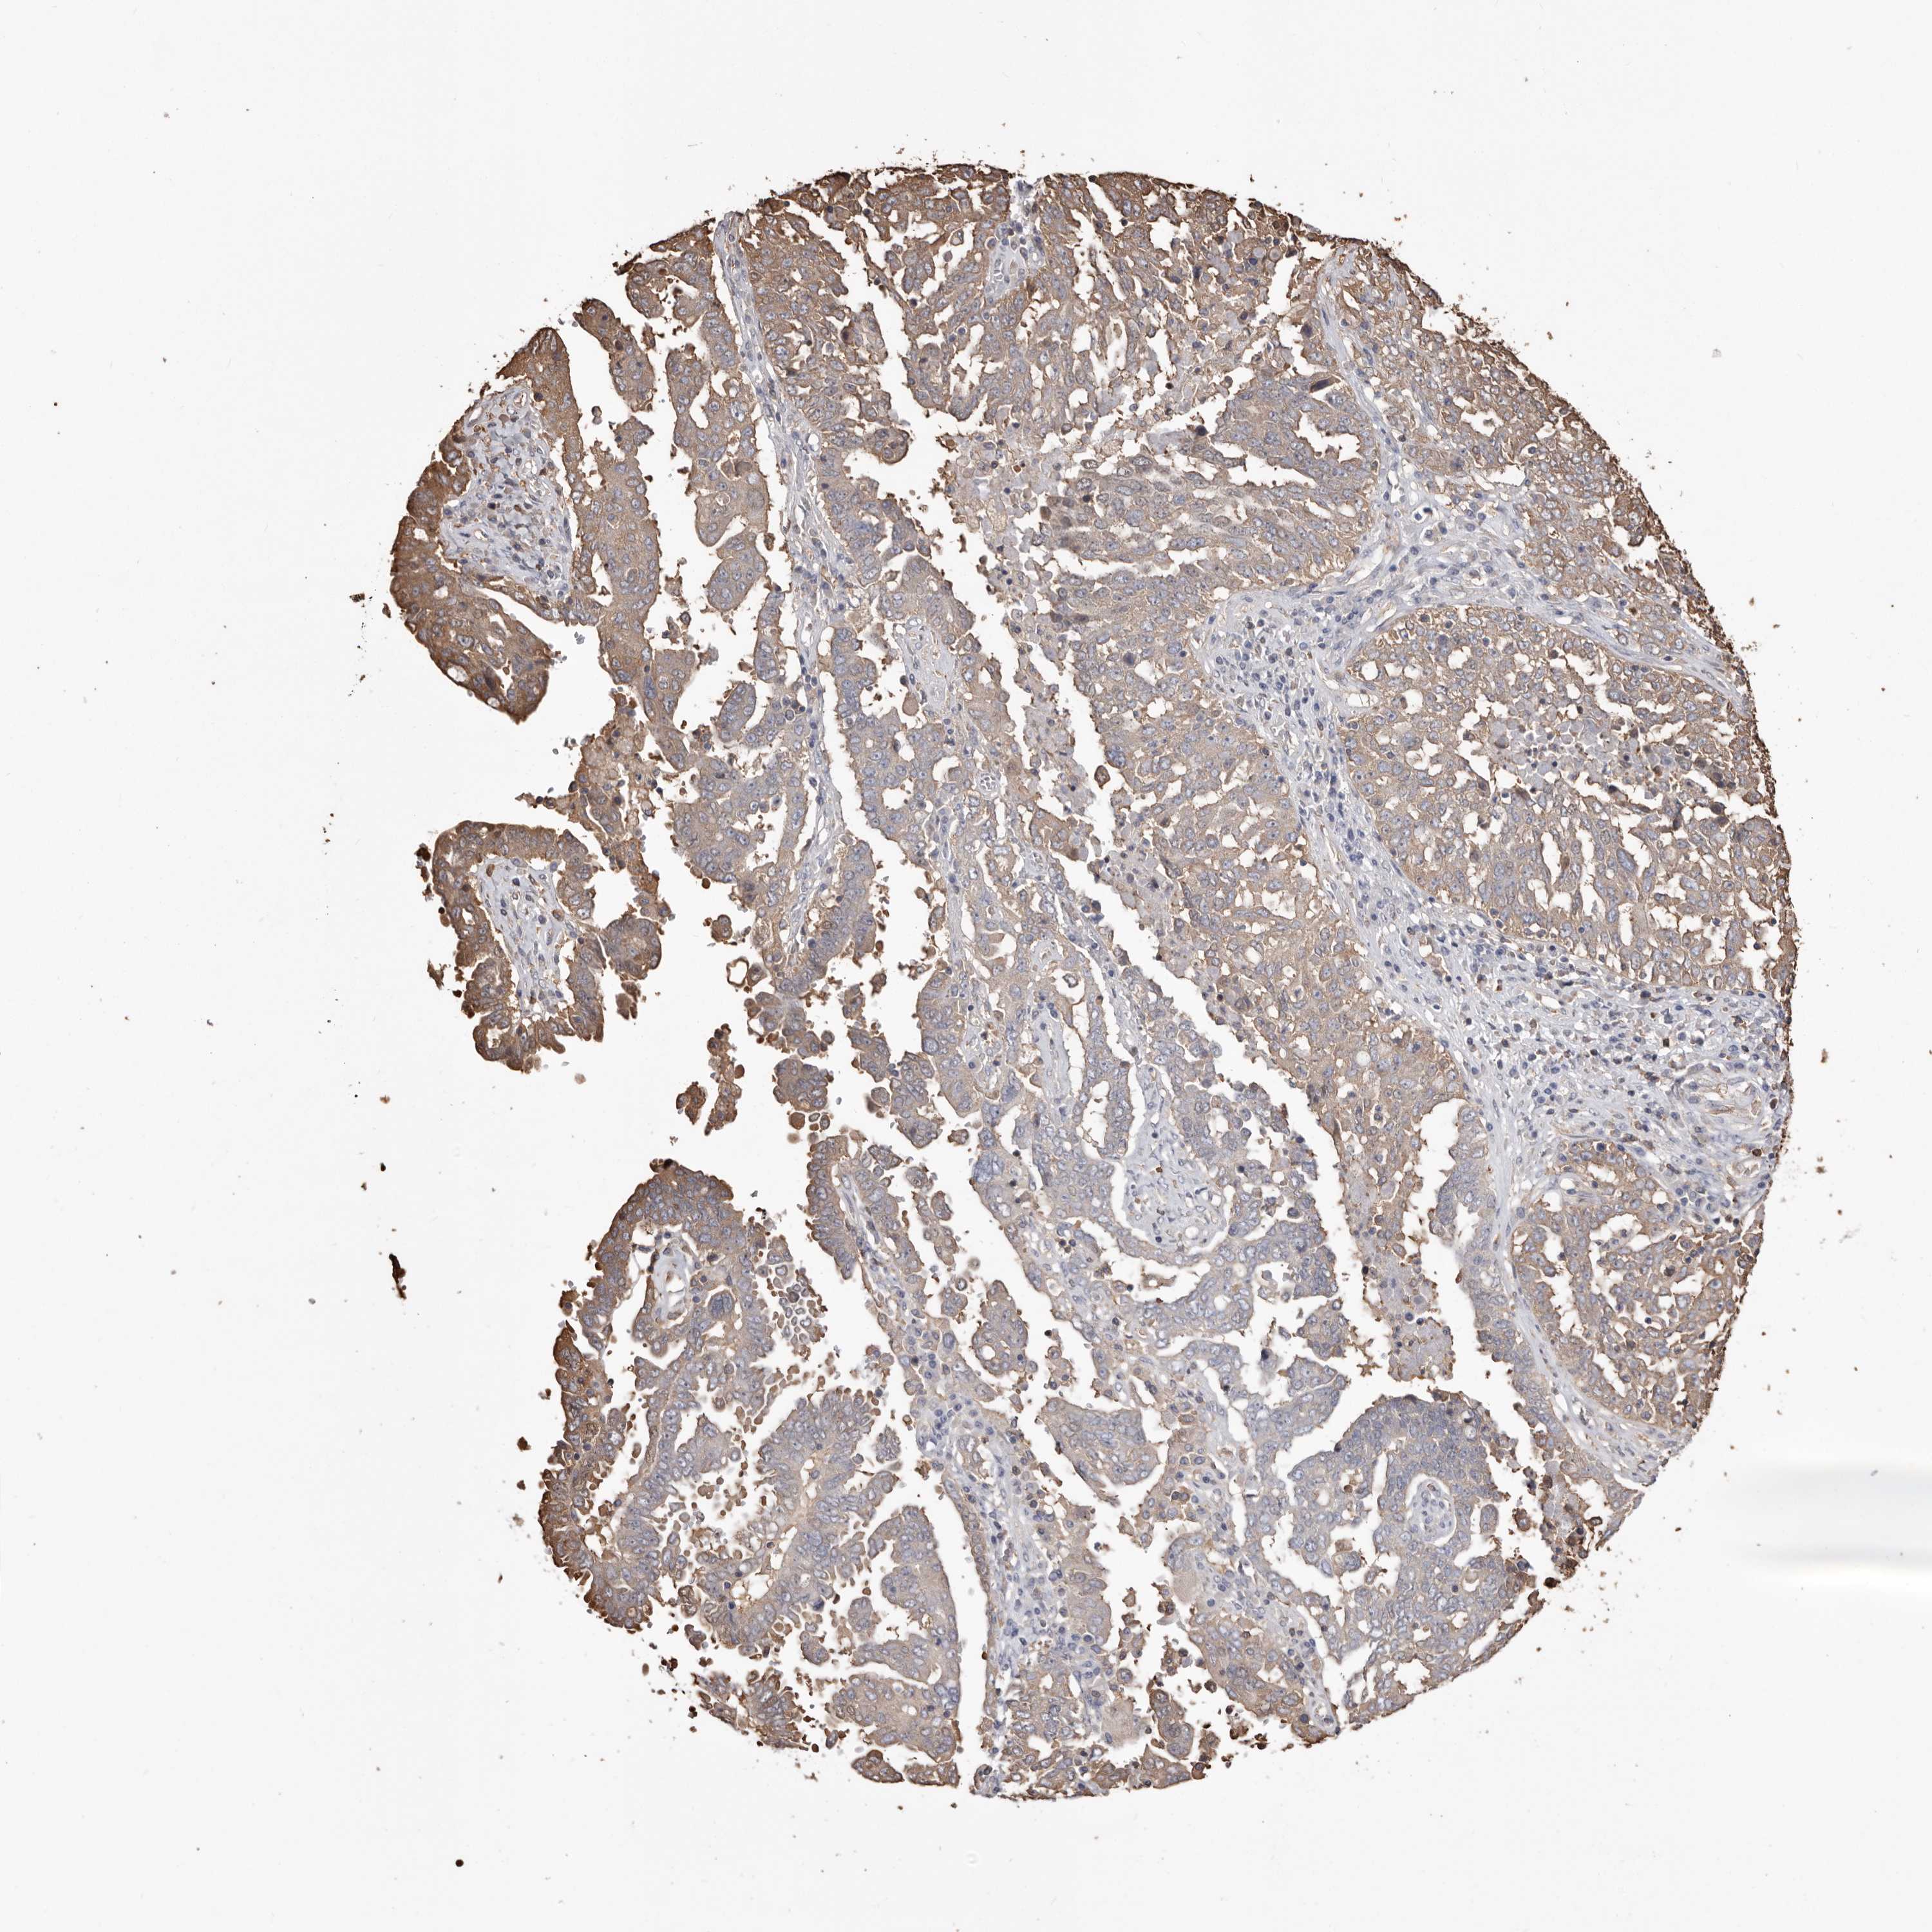

OVARIAN CANCER - Protein expressioni

A mouse-over function shows sample information and annotation data. Click on an image to view it in a full screen mode. Samples can be filtered based on level of antibody staining by selecting one or several of the following categories: high, medium, low and not detected. The assay and annotation is described here.

Note that samples used for immunohistochemistry by the Human Protein Atlas do not correspond to samples in the TCGA dataset.

Antibody stainingi

Antibody staining in the annotated cell types in the current human tissue is reported as not detected, low, medium, or high, based on conventional immunohistochemistry profiling in selected tissues. This score is based on the combination of the staining intensity and fraction of stained cells.

Each image is clickable and will lead to virtual microscopy that enables deeper exploration of all samples and also displays staining intensity scores, fraction scores and subcellular localization as well as patient and tissue information for each sample.

Antibody HPA029501

Antibody CAB019421

Staining

High

Medium

Low

Not detected

Intensity

Strong

Moderate

Weak

Negative

Quantity

>75%

75%-25%

<25%

None

Location

Nuclear

Cytoplasmic/membranous

Cytoplasmic/membranous,nuclear

Cystadenocarcinoma, serous, NOS

Carcinoma, endometroid

Cystadenocarcinoma, mucinous, NOS

Carcinoma, NOS